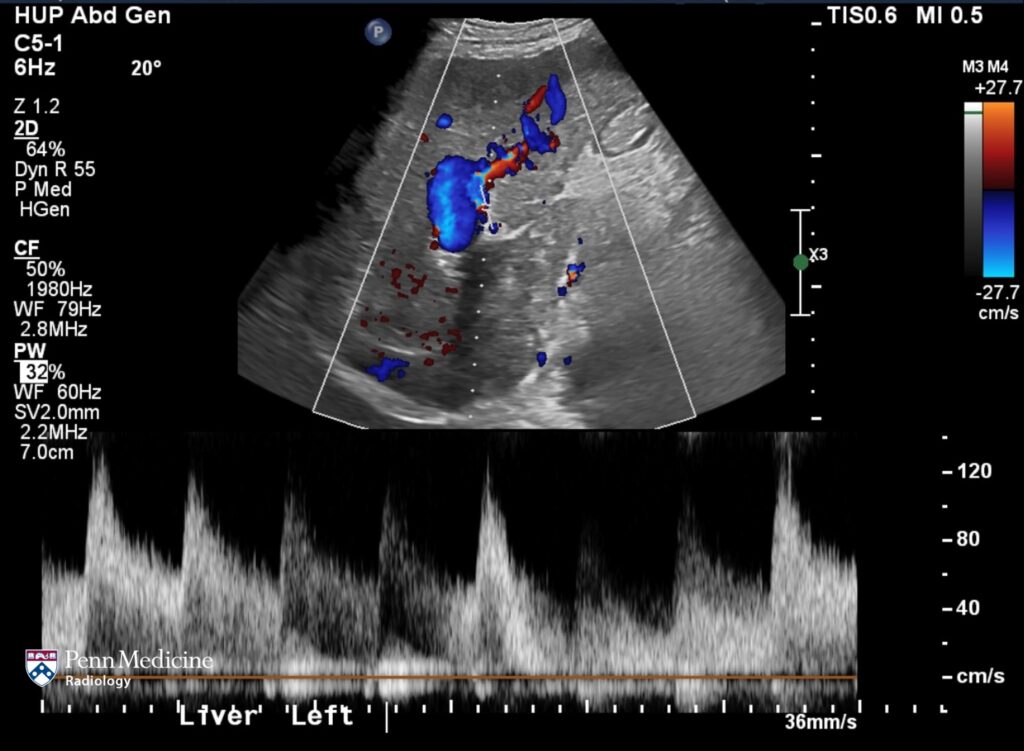

32-year-old man with incidental liver lesion

A 32-year-old man presented for further evaluation of an incidental liver lesion.